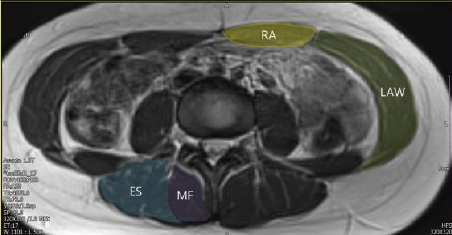

Relationship between Cross-Sectional Area and Function of Core Muscles: An MRI Study